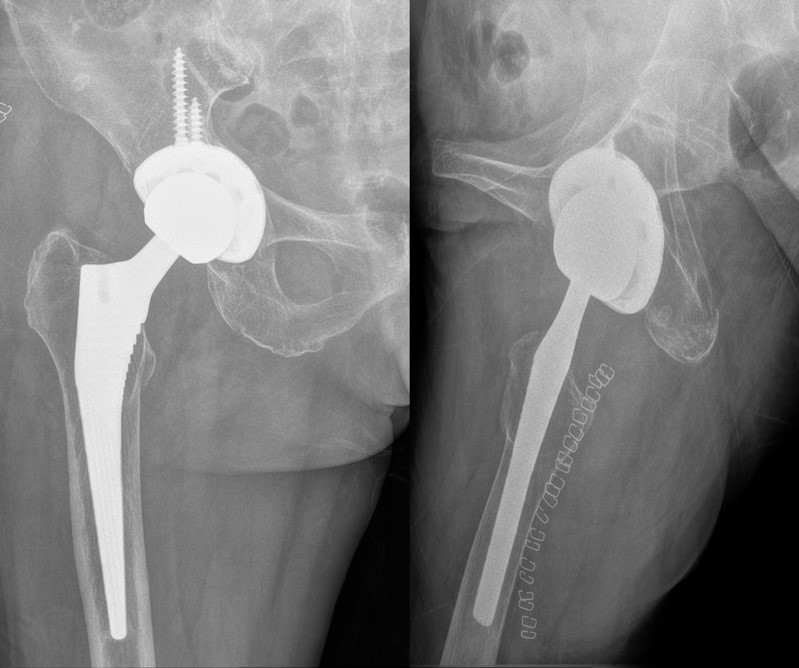

术前右髋关节正侧位片,提示髋臼假体外展角、前倾角异常

翻修术后复查X线片提示髋臼侧假体外展角及前倾角理想,两下肢等长